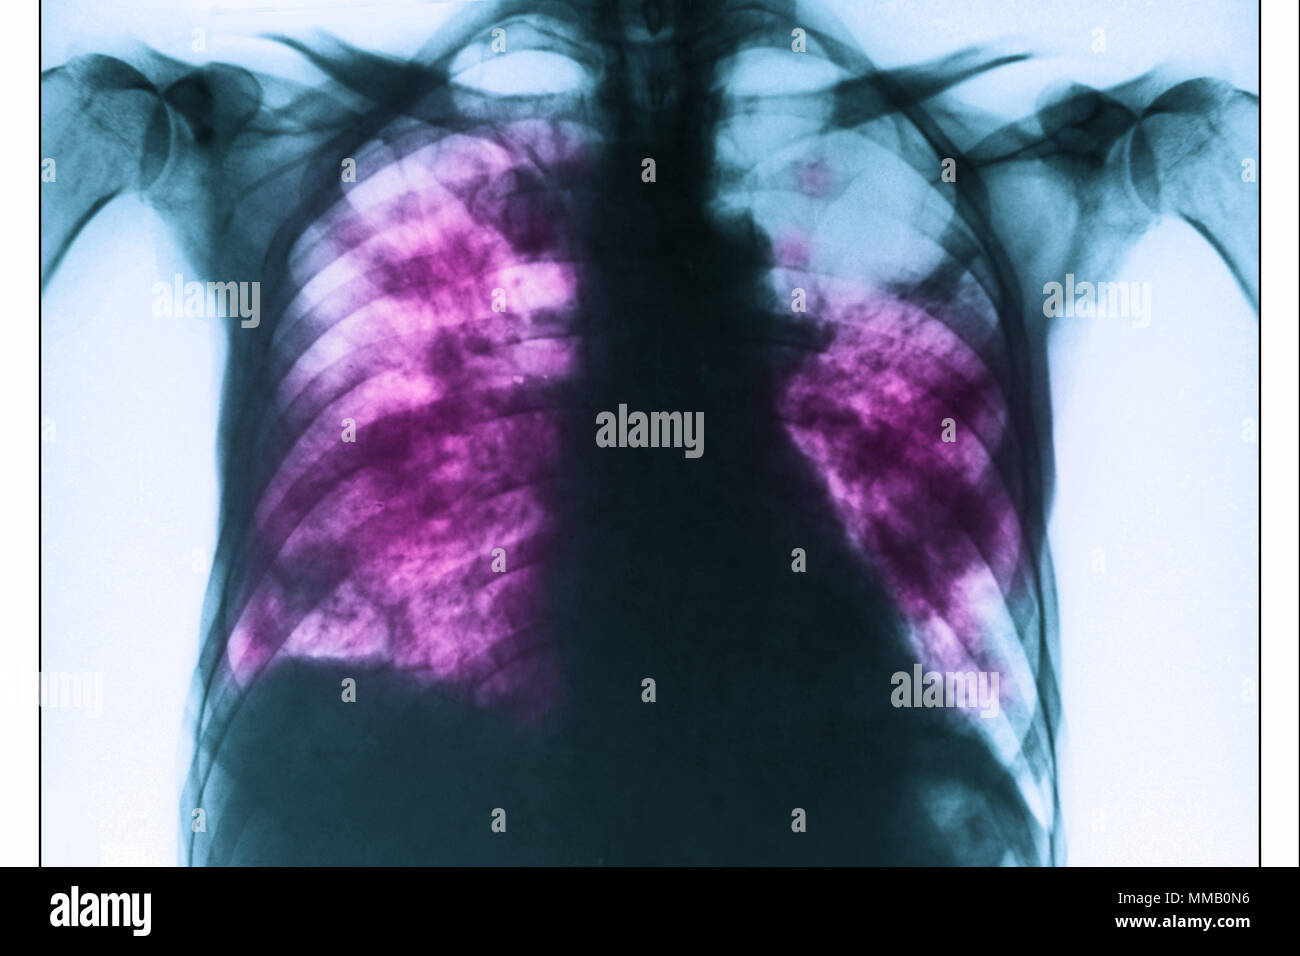

Pneumonia Chest X ray Kaggle Mycoplasma Pneumonia Chest X Ray The aim of the current study was to review the chest radiographic and ct features of serologically proven m. Dense medial opacity in the right upper zone causing. Pneumoniae pneumonia in 28 patients and to compare the two imaging. The purpose of this study was to clarify the pattern of abnormalities with. Mycoplasma Pneumonia Chest X Ray.

Four Categories Of Chest X Rays Of Mycoplasma Pneumon vrogue.co Mycoplasma Pneumonia Chest X Ray Pneumoniae pneumonia in 28 patients and to compare the two imaging. The aim of the current study was to review the chest radiographic and ct features of serologically proven m. Dense medial opacity in the right upper zone causing. The purpose of this study was to clarify the pattern of abnormalities with. Mycoplasma Pneumonia Chest X Ray.